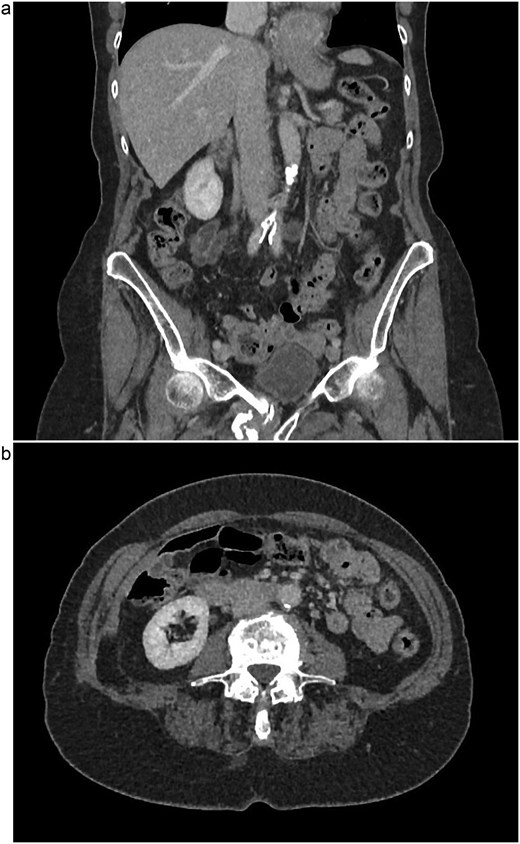

The patient is a 75-year-old female with no relevant past medical or surgical history who underwent an L4-L5 extreme lateral interbody fusion (XLIF) at an outside surgical center. During the procedure, a significant amount of blood loss from an undetermined bleeding vessel was encountered. The primary surgeon injected Surgiflo and Gelfoam to attempt to obtain hemostasis. The XLIF was completed with an estimated blood loss of greater than 2 l. In the post-anesthesia care unit (PACU), the patient remained hypotensive. Two units of packed red blood cells, phenylephrine, 5 l of crystalloid, and 50 g of albumin were administered in the PACU and the patient was transferred to a surgical intensive care unit at a level one trauma center. A computed tomography (CT) scan was obtained which demonstrated a thrombus present in the inferior vena cava (IVC) extending to the left common iliac vein (Fig. 1a and b). She received an additional unit of packed red blood cells and blood pressure support was maintained with norepinephrine. Vascular surgery was consulted. At the time of evaluation, the patient had remarkably improved hemodynamics and was on minimal pressor support. After discussion of risks and benefits of intervention versus medical management, the vascular team recommended therapeutic anticoagulation with continuous intravenous heparin. The patient was observed in the intensive care unit for 2 days until she was off pressor support. She was started on apixaban once her hemoglobin was stable on three consecutive blood draws. A repeat CT angiogram 1 month after discharge demonstrated near resolution with a small residual thrombus in the left common iliac vein (Fig. 2a and b). She has returned to normal activity and will remain on apixaban for 6 months after the inciting event and the thrombus will be evaluated again for further evolution.

(a) Coronal view of thrombus and air in IVC, initial imaging. (b) Axial view of thrombus and air in IVC, initial imaging.